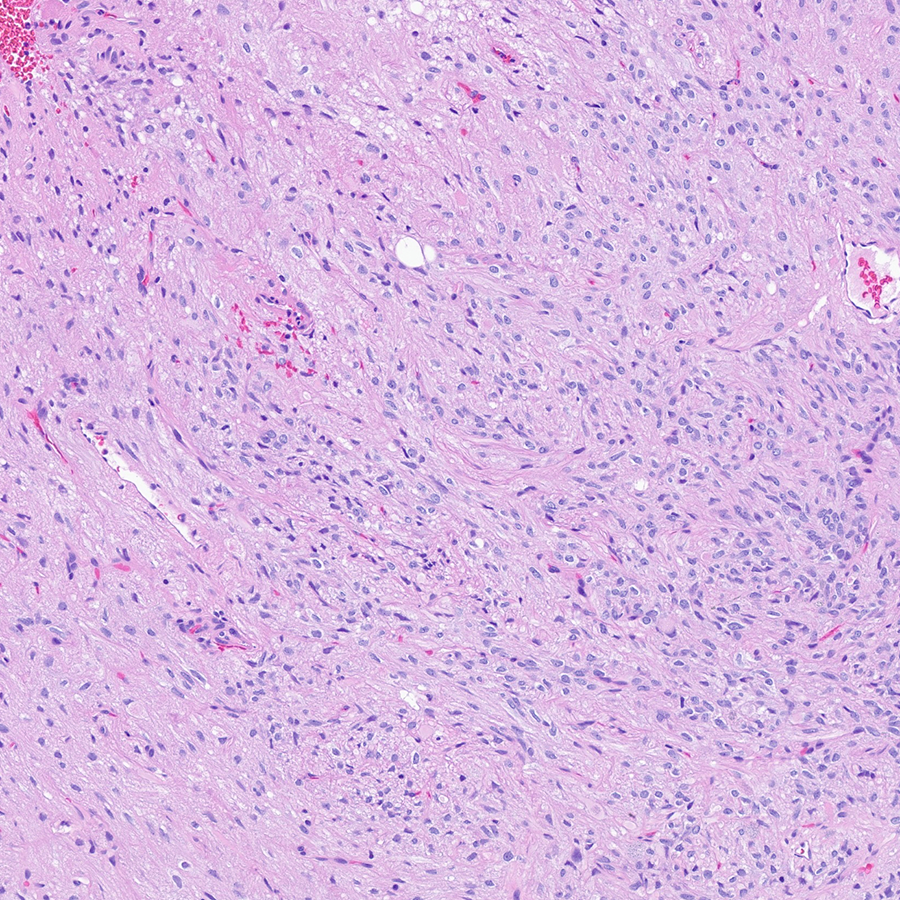

Craig Horbinski

12 days

Sellar mass. Diagnosis? #pathology #neuropath #pathtwitter

7

10

41